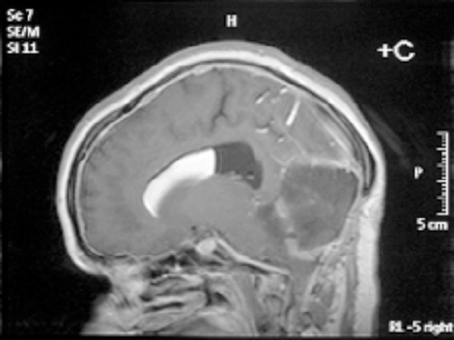

As usual, the patient recovered rapidly to GCS 15, headache free, but this time when she was mobilized after a couple of days in bed there was no deterioration and she managed to progress to the regional rehabilitation hospital and eventually to independent life in the community. She has currently been followed up for six years with no further shunt malfunctions and imaging showing normal ventricular size, complete evacuation of the lipid from the right lateral ventricle and no recurrence of the posterior fossa dermoid cyst (Figures 2,3).

Click below to enlarge

Figure 3: Axial T1-weighted MRI scan showing a functioning right parietal shunt with a decompressed ventricular system. The intraventricular fat has been removed; the cortical sulcal fat remains..